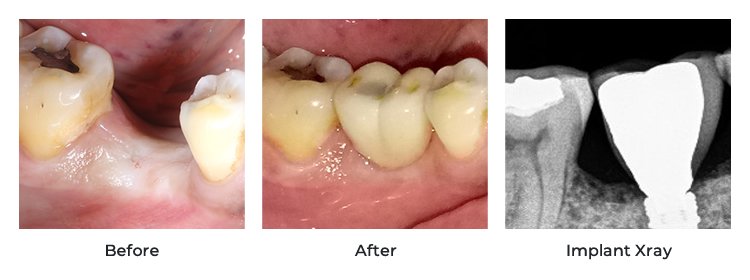

- Patient Reviews and Testimonials: Online reviews on Google, clinic websites, or medical tourism platforms can provide valuable insights into other patients’ experiences. Ask for before-and-after photos.